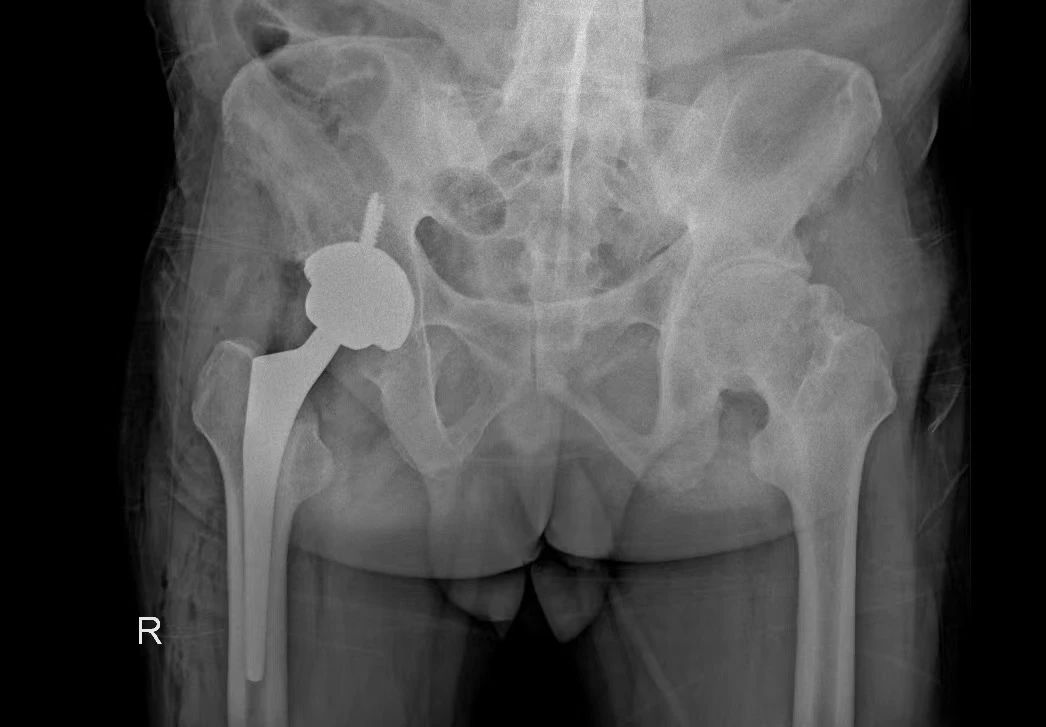

術(shù)后平片

術(shù)中,DAA入路充分顯露髖臼,順利注冊(cè)好標(biāo)記點(diǎn),機(jī)械臂精準(zhǔn)地定位到預(yù)期規(guī)劃位置,輔助完成髖臼的磨銼和髖臼杯放置,羅軍主任與手術(shù)團(tuán)隊(duì)成員參照術(shù)前規(guī)劃,協(xié)同機(jī)器人“作戰(zhàn)”,對(duì)髖臼窩進(jìn)行了亞毫米級(jí)的精確磨銼,將髖臼杯的安裝角度控制到了1°以?xún)?nèi),達(dá)到了精確的效果,手術(shù)圓滿(mǎn)完成。

術(shù)后,在科室醫(yī)護(hù)人員及康復(fù)團(tuán)隊(duì)的精心照料下,患者術(shù)后12小時(shí)可以下地走路,術(shù)后一周棄拐行走恢復(fù)良好并順利康復(fù)。